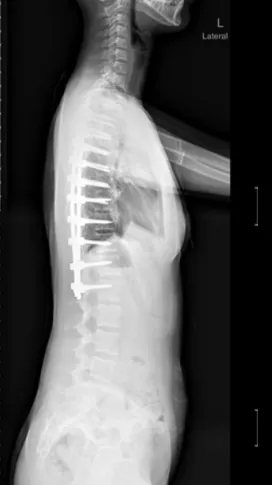

▷早发性脊柱侧凸

早发性脊柱侧凸(EOS),指10岁之前因各种原因导致的脊柱侧凸畸形,如婴幼儿特发性脊柱侧弯、先天性脊柱侧凸、神经肌源性脊柱侧凸等。

▲ 男,14岁,早发性脊柱侧弯、先天性脊柱畸形